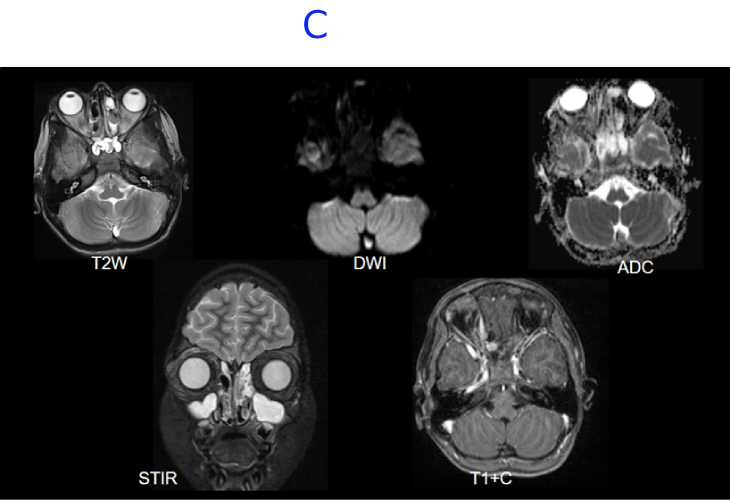

C. MRI BRAIN WITH IV CONTRAST - DAY 11- STATUS POST DECOMPRESSION

C. Near complete resolution of the right globe proptosis.Interval reduction in the thin enhancing collection along the medial wall of right orbit demonstrating minimal diffusion restriction.Near complete resolution of the extensive T2/STIR hyperintense edema noted in right periorbital soft tissue and orbital compartments with minimal residual edema in the preseptal space.Near complete resolution of the soft tissue stranding involving postseptal fat, surrounding the extraocular muscles.